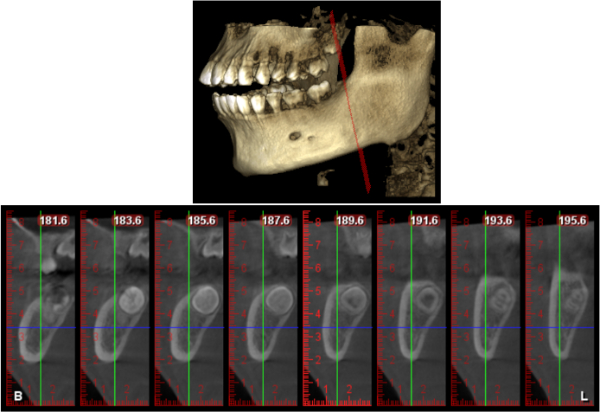

牙科專用的3D電腦斷層攝影;與傳統醫療電腦斷層相比較,輻射劑量只有一般電腦斷層的1/50;切片厚度一般醫療電腦斷層是2.0公厘,牙科3D電腦斷層則只有0.1公厘,就診當天馬上拍攝電腦斷層,馬上獲得立體影像。

電腦斷層顯示下齒槽神經距離遠